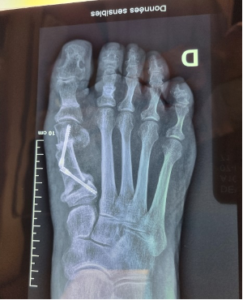

Traitement de l’hallux valgus par chirurgie mini-invasive du pied

La chirurgie mini-invasive et percutanée du pied est une technique moderne utilisée notamment dans le traitement de l’hallux valgus, aussi appelé « oignon du pied ». Elle repose sur de petites incisions, généralement limitées à quelques millimètres ou 1 à 2 cm, afin de corriger certaines déformations de l’avant-pied sans recourir à de larges ouvertures.

Dans le cadre du traitement de l’hallux valgus, le chirurgien utilise des instruments spécifiques, conçus pour travailler avec précision à travers ces incisions réduites. Comme l’intervention se fait sans exposition complète des structures, chaque geste est contrôlé en temps réel grâce à un amplificateur de brillance, une radiographie dynamique permettant de visualiser la correction osseuse pendant l’opération.

Cette approche vise à réaligner le gros orteil, réduire la douleur, améliorer le chaussage et limiter l’agression des tissus, lorsque l’indication chirurgicale est adaptée.

Dans le cadre du traitement de l’hallux valgus, l’objectif est de réaligner le gros orteil, de corriger la déformation osseuse et d’améliorer le chaussage. L’indication dépend toujours de l’examen clinique, des radiographies et de la gêne ressentie par le patient.

Hallux valgus sévère : ostéotomie bifocale percutanée

Hallux valgus sévère : ostéotomie bifocale percutanée L’hallux valgus est l’une des déformations les plus fréquentes de l’avant‑pied. Elle se caractérise par une déviation progressive du gros orteil vers l’extérieur, associée à un déplacement du premier métatarsien vers l’intérieur. Avec le temps, cette modification de l’alignement du pied peut entraîner